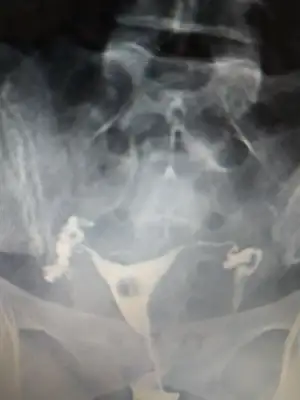

Onun hatlar karışık biraz. Çekim sonrası radyologun mesai saati bittiği için rapor yetişmemiş. Pazartesi alacak sonucunu. Kendi doktoru tüplerden birinde tıkanıklık var gibi konuşmuş ama başka doktorlara da göstermiş, basınçla açılmış demişler